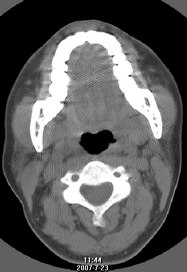

以下是引用还珠格格在2007-7-31 19:32:00的发言:[br]右侧鼻前庭内可见软组织块影,部分鼻中隔包绕其内,邻近骨质未见明显吸收破坏,考虑 1、鼻息肉可能性大 内翻乳头状廇不除外。期待结果。

以下是引用zjzjr在2007-7-31 20:29:00的发言:[br]右侧鼻前庭内可见软组织块影,部分鼻中隔包绕其内,邻近骨质未见明显吸收破坏,考虑 1、鼻息肉可能性大 内翻乳头状廇及肉芽肿类病变除外。期待结果。